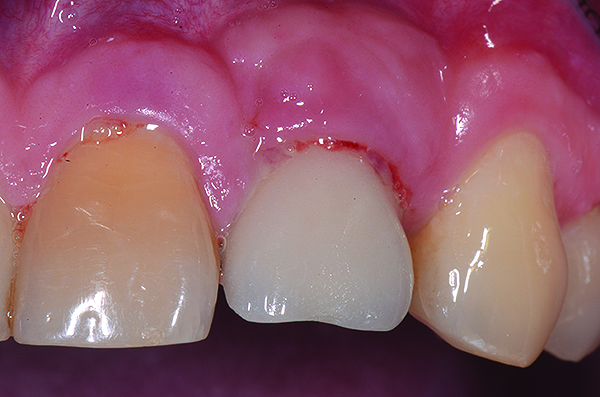

Fig 7. Four weeks following nonsurgical treatment, the area is healthy as probing depths are now shallow and bleeding is absent. Treatment involved scaling of the area, which removed all plaque and a slight amount of cement, and irrigation with an anti-inflammatory hydrogel.

Figure 7